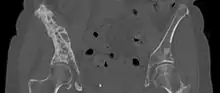

3D rendered CT scan of bone metastases of the hip bone, in a 60 year old woman with parotid gland cancer. Large lesions are seen on the ilium on the more distant side. Involvement of the vertebral column has caused a compression fracture.